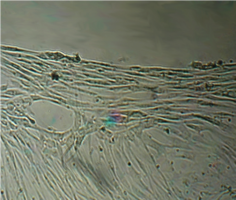

Наблюдение через сутки показало, что фибробласты пристают к дну культуральной чашки преимущественно вблизи образцов, при этом тела клеток располагаются вдоль периметра исследуемых дисков (рис. 38).

В отдаленных зонах фибробласты образуют редкий равномерный монослой, плотность которого в последующие сроки увеличивается с обычной для данной культуры скоростью, поэтому к концу наблюдения плотность насыщения не достигается.

Со вторых суток вблизи образцов фибробласты образуют второй слой клеток, а на четвертые сутки мы видим вокруг них такой же «валик», который мы наблюдали в 5 серии экспериментов (табл. 16).

В течение всего срока наблюдения фибробласты сохраняют характерную морфологию, скорость и характер роста (рис. 41).